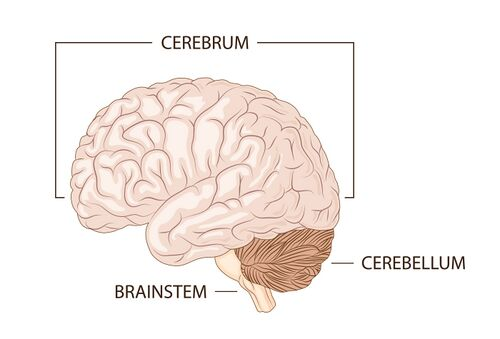

What are cerebrum higher brain functions?

sensory, consciousness,motor control

Which brain region is responsible for autonomic/reflex centers (breathing, cardiac rhythm)?

Brainstem

Which brain region is responsible for coordination of movement (balance)?

Cerebellum